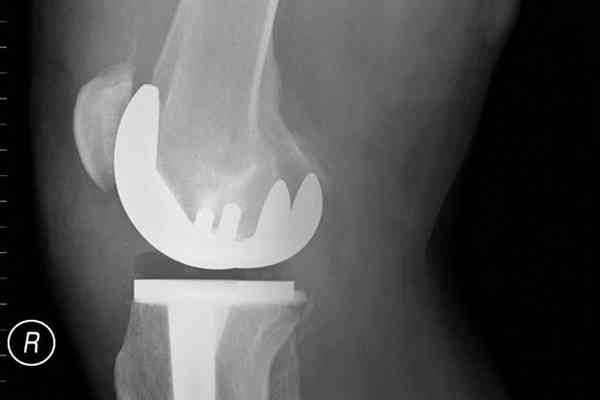

CAO facilities offer a full range of orthopaedic specialties for complete diagnosis and treatment of all musculoskeletal conditions and injuries.